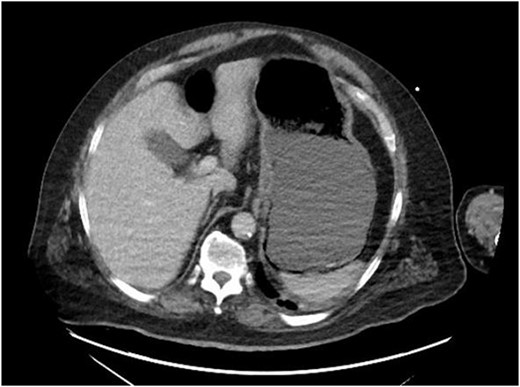

On evaluation, the patient was afebrile, tachycardic to 107 bpm, with BP 112/63 and RR 21. On exam, he appeared diaphoretic and had left upper quadrant tenderness without rebound or guarding. He was otherwise alert and oriented. His white blood cell count was 22.5 with 13.1 bands, and lactate of 6.2, which improved with IV fluid resuscitation. Computed tomography (CT) abdomen and pelvis demonstrated pneumatosis of the proximal gastric wall (Fig. 1), and mild portal venous gas. He was started on antibiotics and antifungals; a nasogastric tube was placed for decompression, and he was started on parenteral nutrition; however, he failed to improve clinically, with continued abdominal pain and tenderness, and persistent tachycardia. A repeat CT after 5 days of treatment redemonstrated gastric wall pneumatosis (Fig. 2), though with resolution of the portal venous gas.